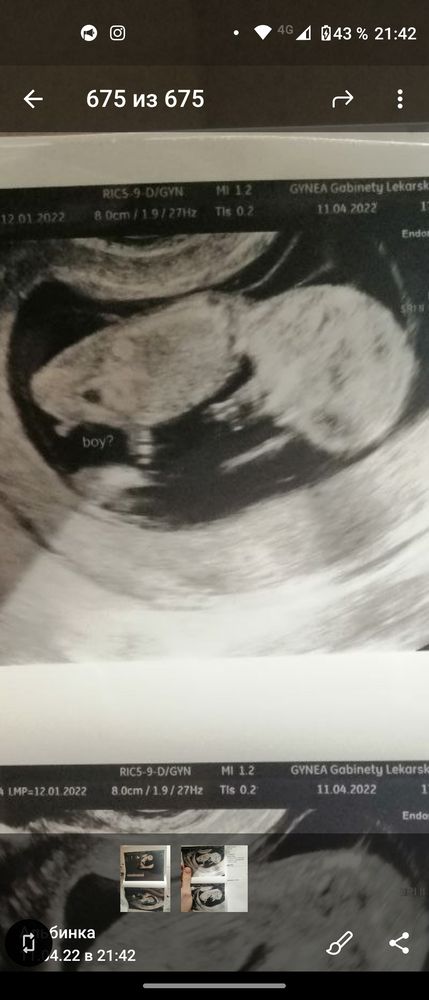

Мальчик или девочка? 12,5 недель

Не видно половой бугорок (там ножка закрывает), но предположу, что мальчик.

Это согнутая ножка, там даже виден сгиб)  Пока совсем не понятно) Подождите до 16-17 недель хотя бы и сделайте повторное узи, если очень хочется быстрее узнать)) если сдайте нипт там и пол будет)